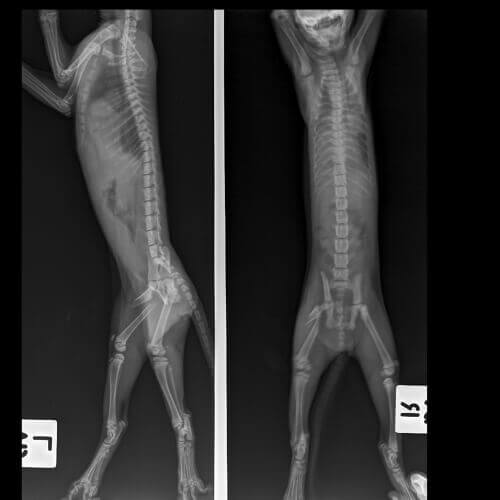

- Röntgenbilder